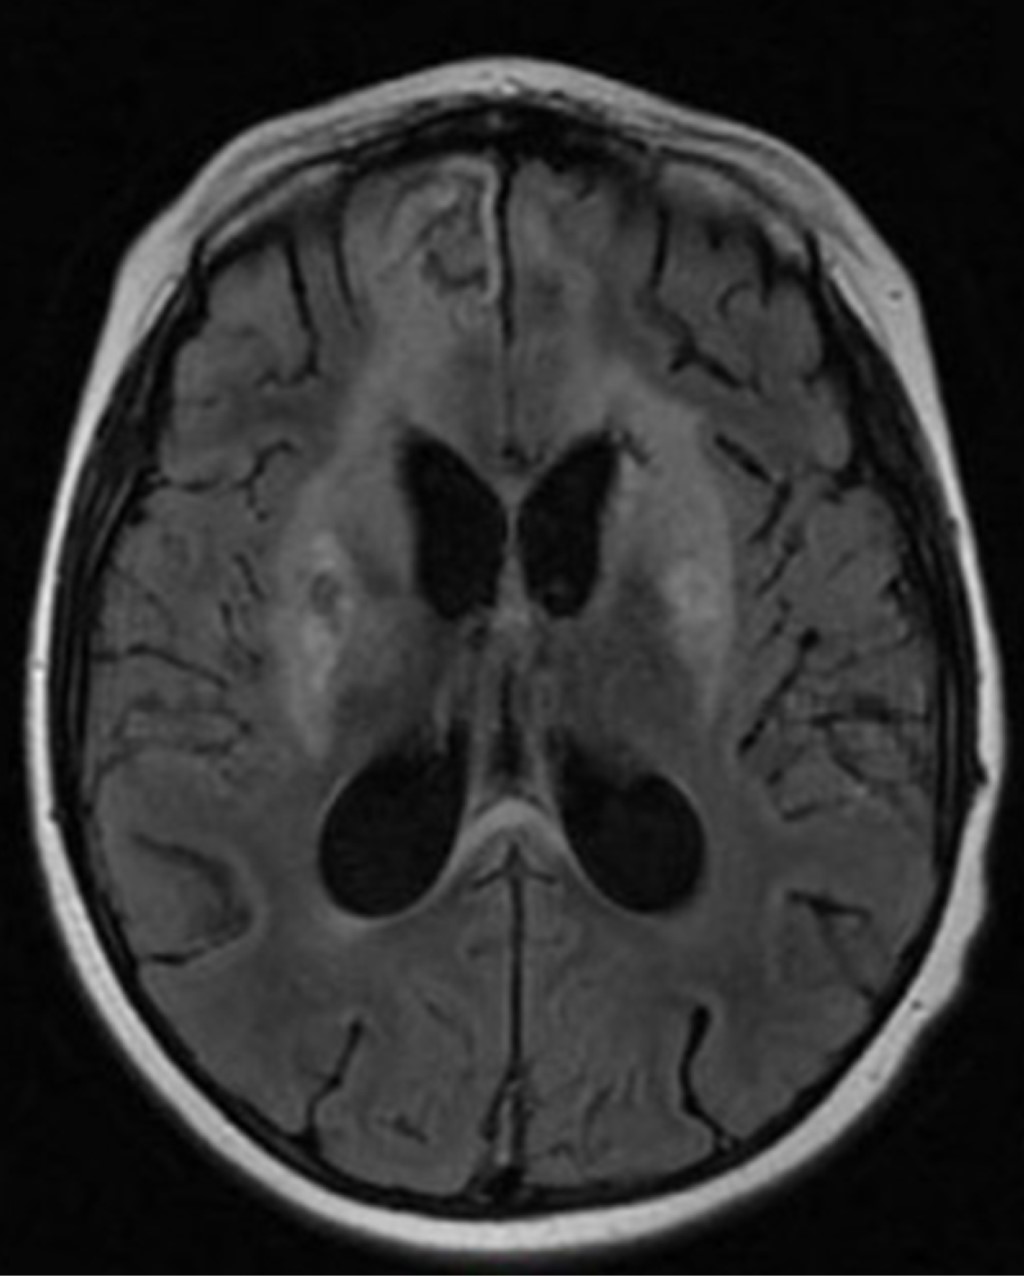

Figure 1